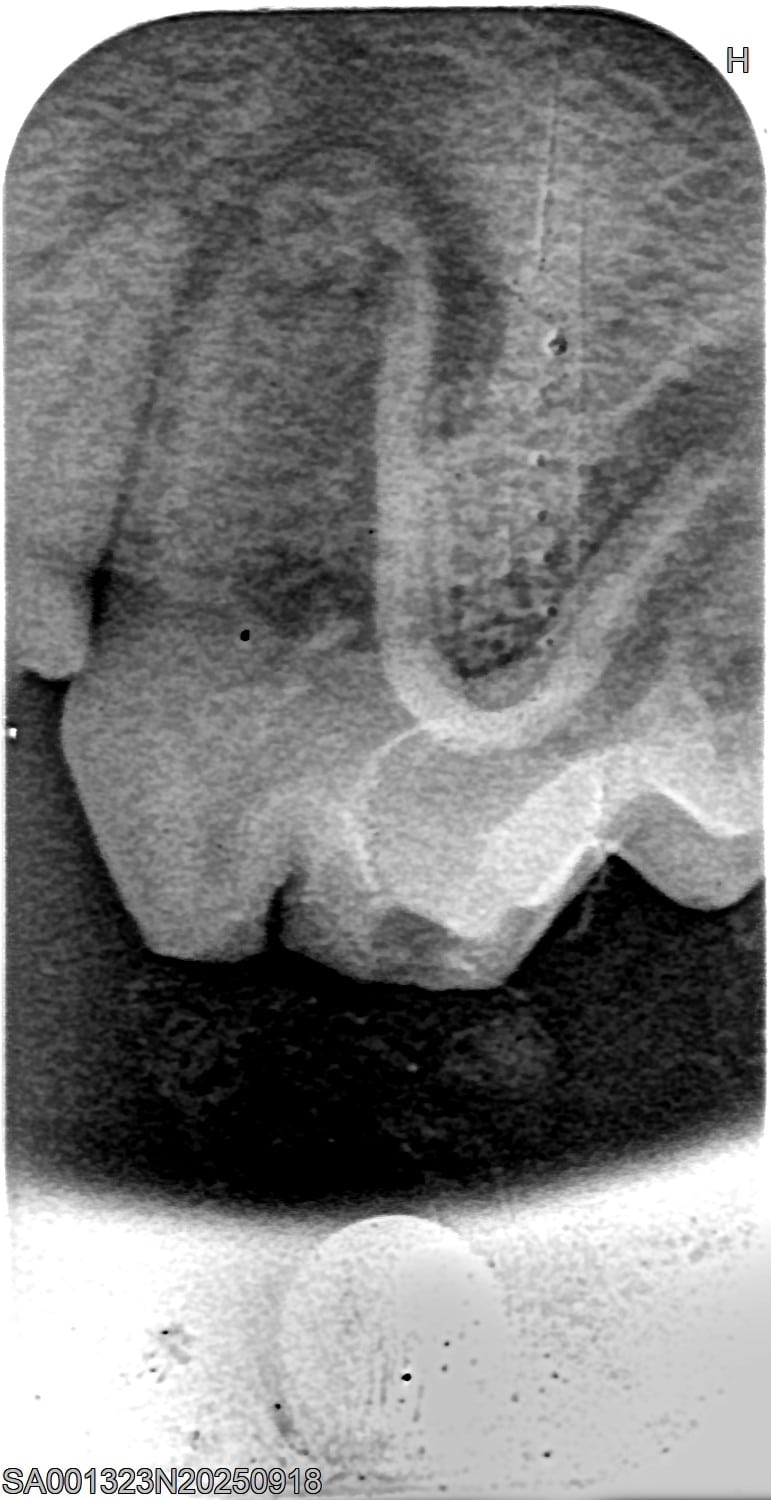

Röntgenbilder

(Fraktur + Wurzelentzündung durch Zahnstein)